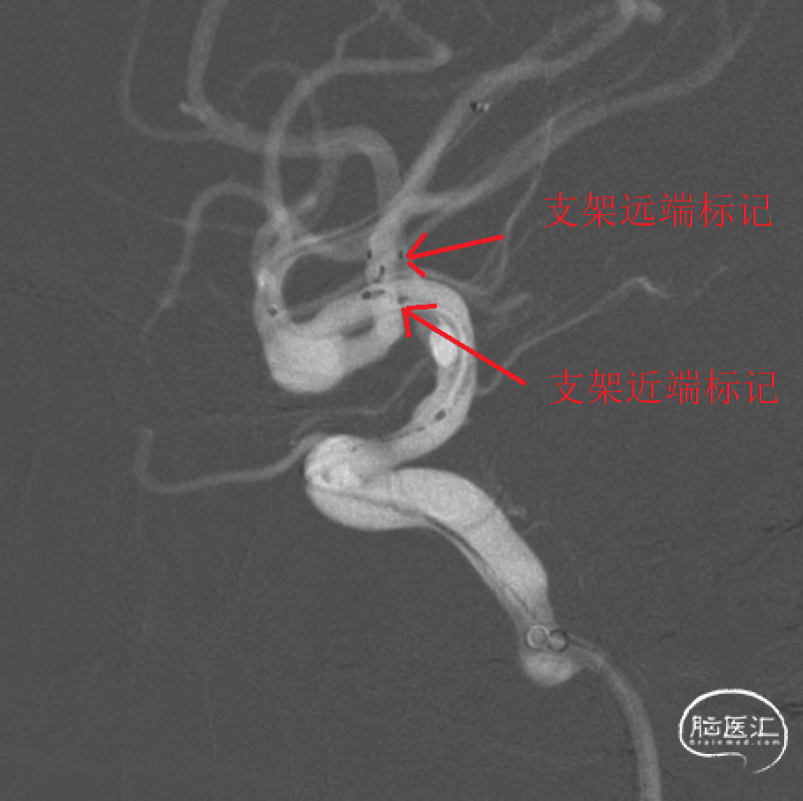

术前影像

术前MRA显示右侧MCA分叉部囊状动脉瘤,具体解剖细节不详。

术前三维测量显示瘤体大小,瘤体约8.16mm*3.27mm,累及上下干, 上干约2.43mm,下干约3.56mm。